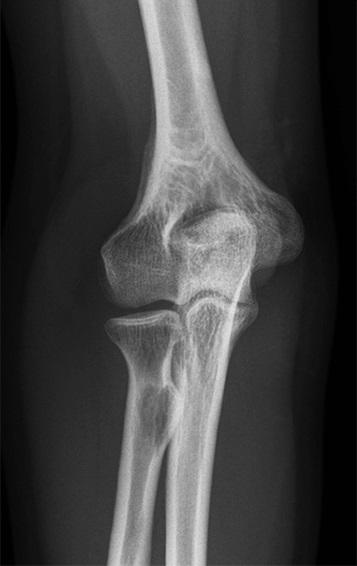

Een 27-jarige vrouw komt naar de SEH vanwege een pijnlijke rechter elleboog na een val met de racefiets. Bij lichamelijk onderzoek zien wij een laceratie aan de posterolaterale zijde van de elleboog en is het olecranon drukpijnlijk.

Wat is uw diagnose?